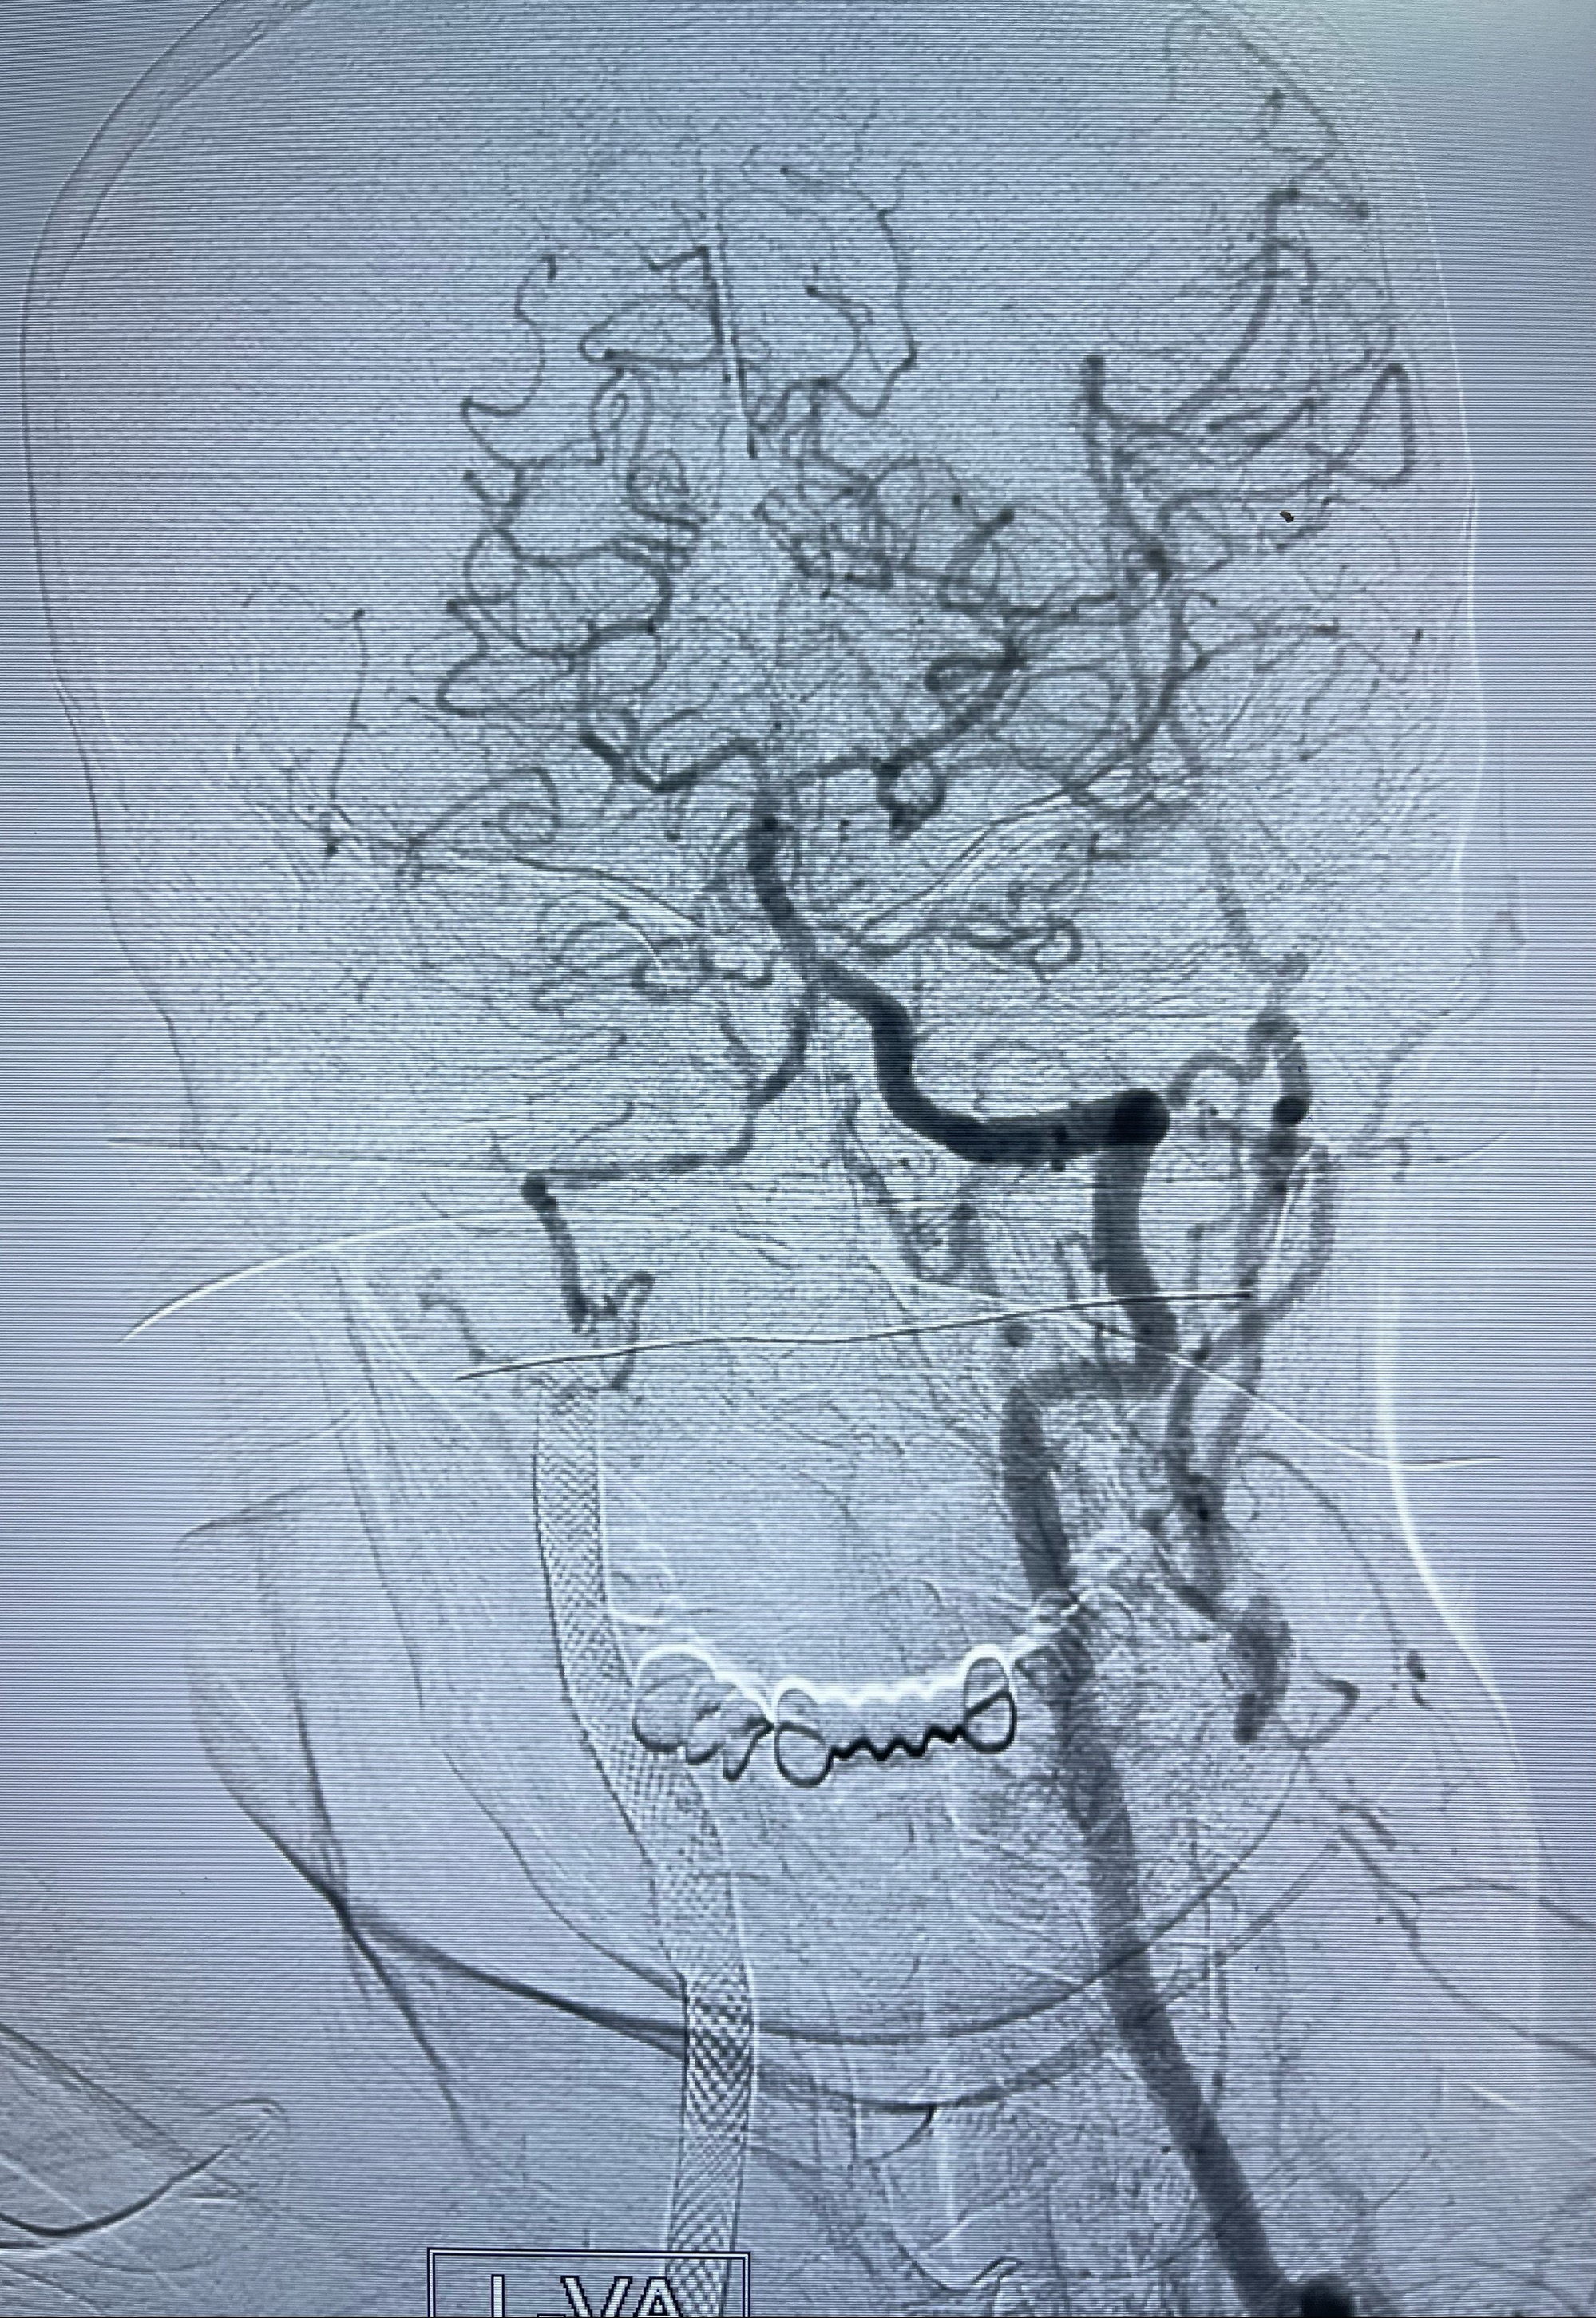

重新行“路径图”,支架导管在微导丝引导下超选择性插入至右侧颈内动脉眼段,4.5-50mmLeo支架释放,远心端位于海绵窦段,近心端位于岩骨段狭窄段以近

即刻造影显示支架贴壁佳

路径图下,5.5-50mmLeo支架导管在微导丝引导下超选择性插入远段Leo支架内

两枚支架部分重叠

多次确认支架位置及打开贴壁情况

支架完全打开,近心端位于原颈动脉支架远心端内